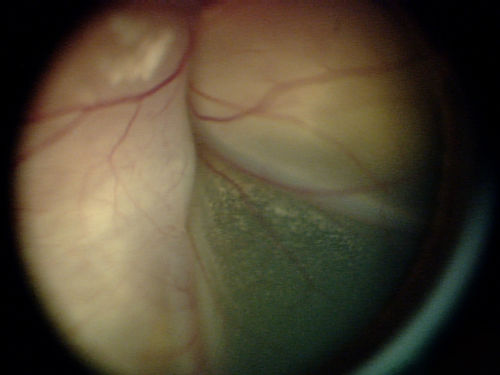

This is an EUA picture of retinoblastoma tumor group D. Tumor group D has high risk of losing the eye. Group D tumors are large or poorly defined with high amounts of seeding.

Tumor Group D

The tumor is large or poorly defined and has a lot of seeding.